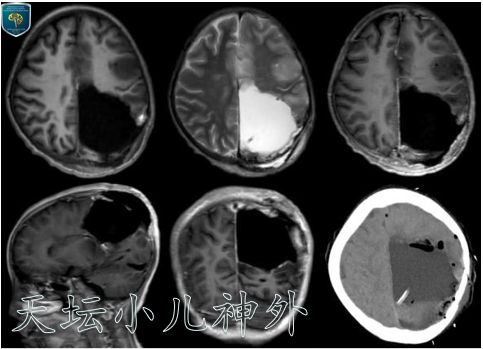

图2患儿2020年8月复查CT/MR显示病变范围扩大,波及左侧丘脑,右下肢出现乏力症状

依据北京天坛医院诊疗常规,该患儿于2020年9月8日行左顶枕开颅病变切除术,术中见肿瘤位于左顶枕部,内至大脑镰,累及胼胝体,色灰黄,血供中等,质地软韧不均,边界不清,镜下近全切除病变,肿瘤周围脑组织保护完好,术腔严密止血,术中出血约500ml,输异体红细胞260ml、异体血浆350ml。术后患儿病情平稳,未再有癫痫发作。病理回报提示:星形细胞瘤,肿瘤侵及软膜下(WHOⅡ级)。 免疫组化结果:Syn(+),NeuN(神经元+),NF(散在+),GFAP(+),Olig-2(散在+),Ki-67(约3-5%),IDH1(-),H3K27M(-)。术后1周患儿出院,恢复好,回当地后续治疗。

图5术后CT/MR,肿瘤切除满意